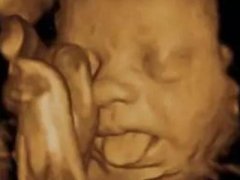

四维彩超那么贵不懂这些就白做了